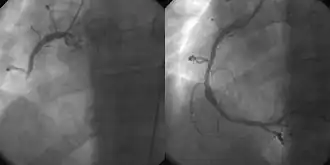

Coronary angiography and angioplasty in acute myocardial infarction (left: Right Coronary Artery [RCA] closed, right: successfully dilated)